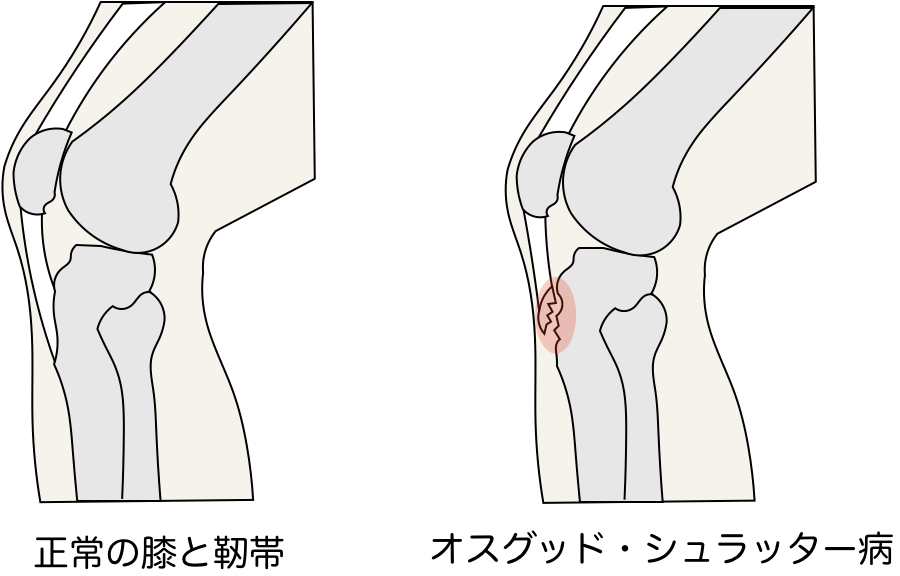

オスグッド・シュラッター病

主に10歳以降の成長期にジャンプやランニングなど膝を伸ばす筋の牽引によっておこる脛骨結節での成長軟骨の障害です。

成長期の子供の膝下(脛骨粗面)は大人と異なり軟骨部分が多く、弱いので運動など繰り返す刺激でダメージを受け、炎症がおきやすいです。

その結果、ひどい場合は軟骨の一部が剥離することがあり腫れていたり、歩くのが困難な場合は重症の可能性があります。

似た疾患にジャンパー膝などがあり、全て膝伸展機構の障害となります。

怪しければ整形外科受診を早めにお勧めします。